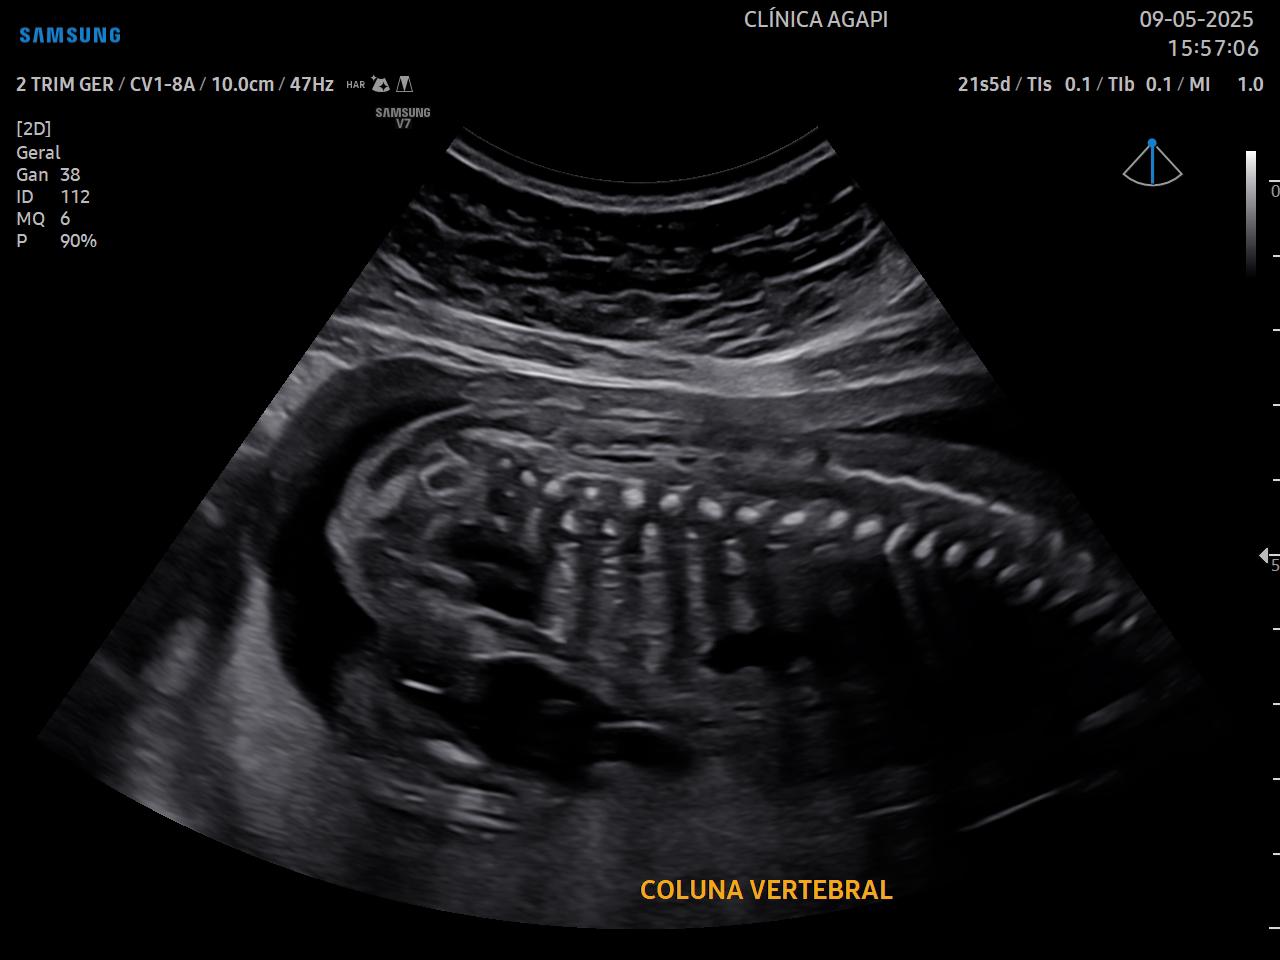

Realizado preferencialmente entre 20 e 24 semanas de gestação, seu objetivo principal é avaliar a anatomia fetal de forma detalhada e detectar possíveis malformações.